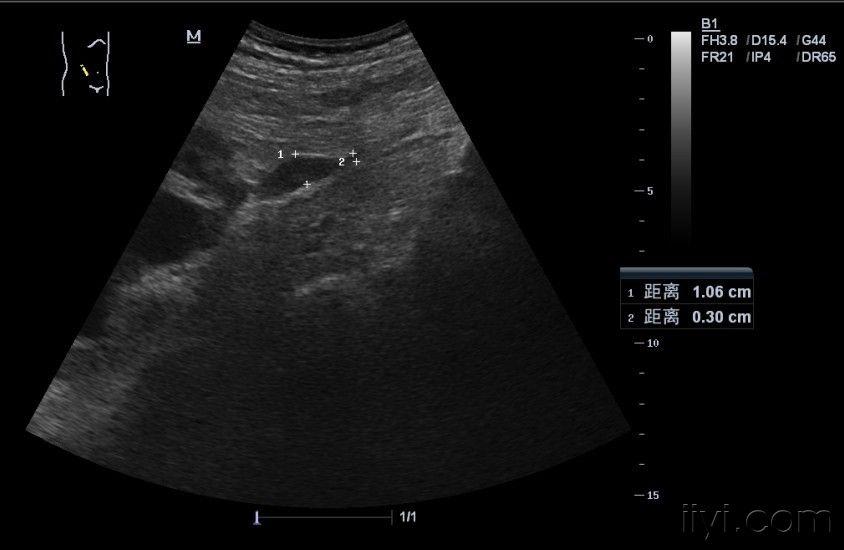

右肾及输尿管上段积水原因 - 超声医学讨论版 - 爱爱

输尿管超声手法图解

输尿管超声分段解剖图